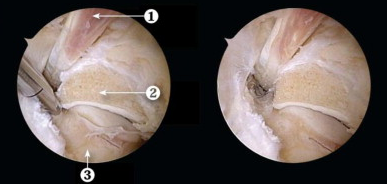

后踝关节镜手术